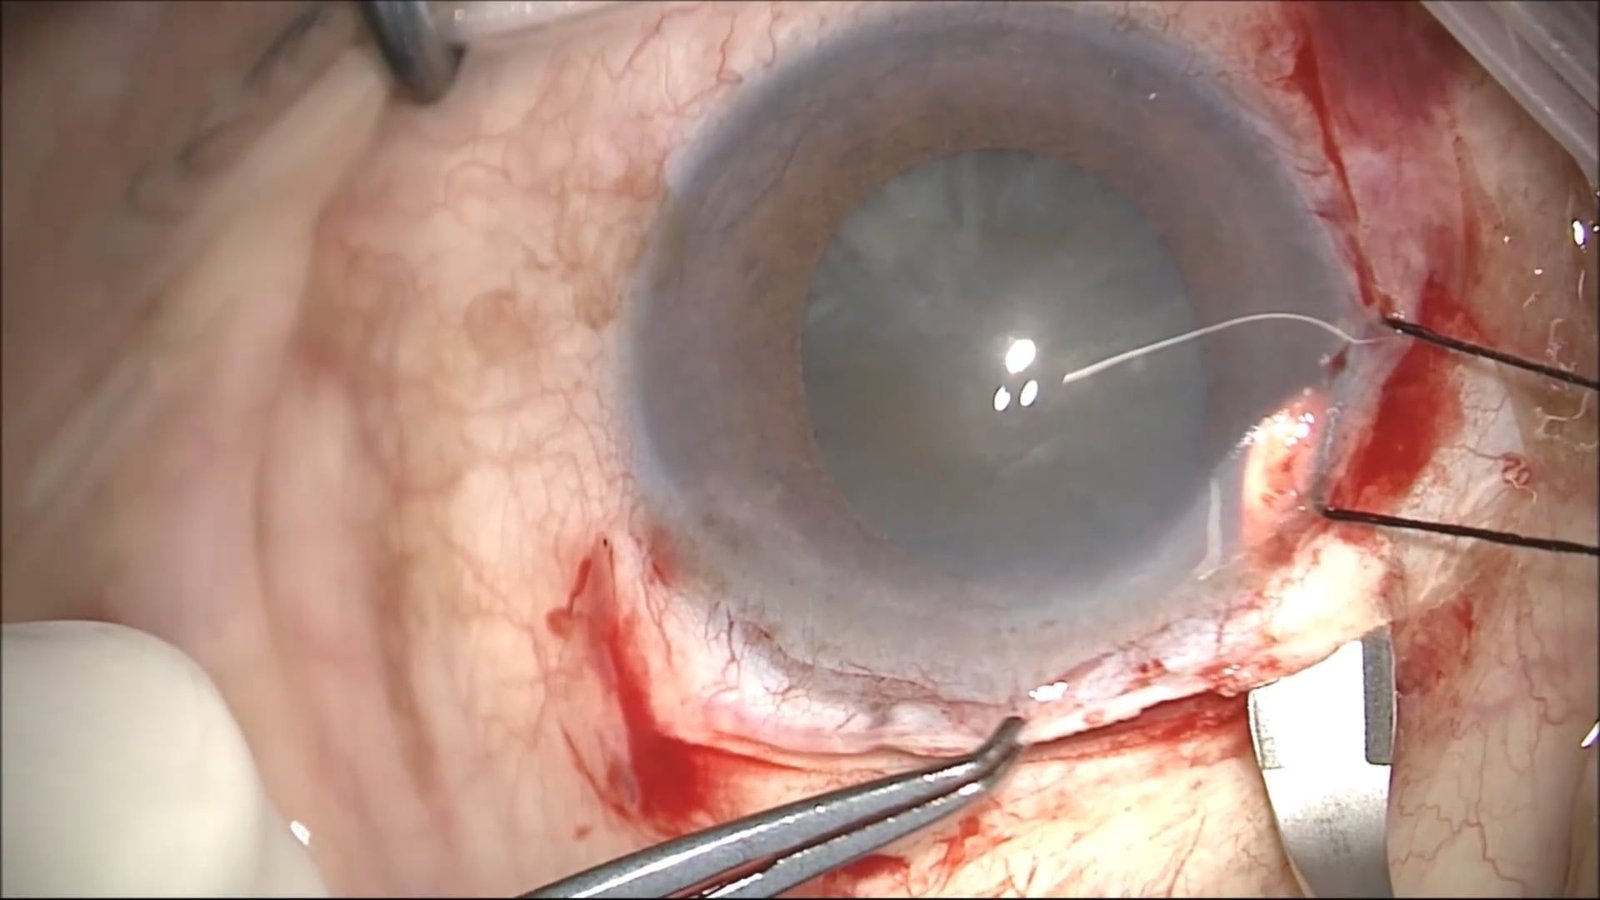

Manejo de catarata Polar Posterior. Golden Ring

Katherine Santos, Emilio Nuñez